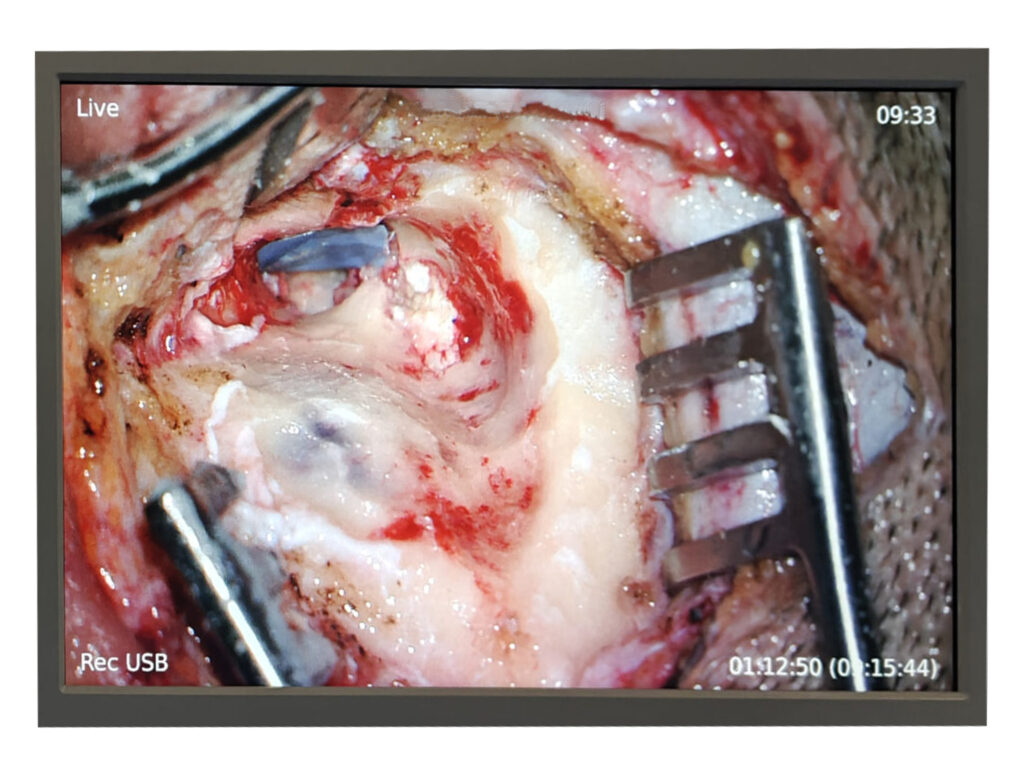

Whitish Cholesteatoma Flakes

Cholesteatoma of the Ear

Tympanomastoidectomy Surgery